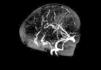

Se realizan las siguientes pruebas complementarias: radiografía de tórax donde se observa discreta cardiomegalia y signos de edema agudo de pulmón; ecografía abdominal (fig. 1) objetivándose un gran trombo que ocupa prácticamente toda la luz de la aorta abdominal desde la parte distal de la mesentérica superior hasta la bifurcación de ambas ilíacas. Ecografía transfontanelar: presencia de un trombo en el seno longitudinal superior, confirmado en la resonancia magnética (fig. 2) y en la angiografía cerebral (fig. 3) realizadas posteriormente.

Figura 3. Angiografía cerebral donde se confirma la presencia de un trombo que ocluye parcialmente el seno longitudinal superior.